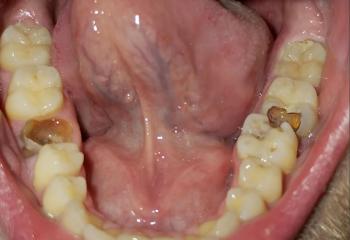

What Is Seen in This Case

The image shows a localized swollen and red gum area near a lower back tooth, with signs of infection along the gumline. The tongue is positioned close to the affected area and appears irritated, likely due to contact with the inflamed tissue or drainage from the infection.

The tooth structure looks intact, but the surrounding gum tissue is clearly unhealthy.

This case shows a localized gum abscess near a lower molar, with early involvement of nearby soft tissues. Early drainage and cleaning usually result in good healing outcomes.